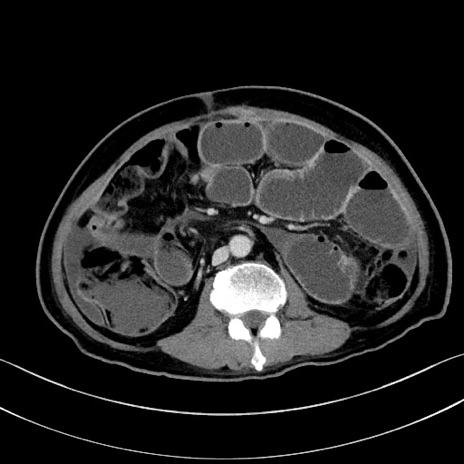

症例28(横断像)

【症例】60歳代男性

【主訴】嘔吐

【現病歴】胃癌にて胃全摘後。食思不振が悪化し、夜中に嘔吐することがある。

【既往歴】胃癌、胃全摘、脾摘、胆摘後

【データ】WBC 5900、CRP 10.56